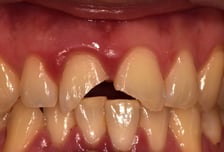

"빠진 치아, 뿌리 말고 머리 잡으세요" 상황별 치아 응급상황 대처법

5월은 어린이날, 부처님오신날 등 각종 공휴일로 이른바 '황금연휴'가 이어진다. 또, 화창한 날씨와 가정의 달을 맞아 국내외 가족여행을 떠나는 경우도 많다. 그런데 연휴 기간에 여행지에서 치아가 부러지거나 수복물이 빠지는 등의 응급상황이 발생하면 어떻게 대처해야 할까? 나아가 국내가 아닌 해외에서 이런 일이 발생한다면 고려할 수 있는 응급처치 방법에는 어떤 것들이 있을까. 서울대치과병원 원스톱협진센터 김욱성 교수(치과보존과 전문의), 구강악안면외과 한정준 교수(치과응급진료실장)와 함께 연휴 기간에 발생한 치아 응급상황에 따른 대처 방법을 알아본다. ━부러진 치아 식염수에 담근 채 치과 가야━ 과거에 치료받았던 수복물이나 보철물 등의 치과재료가 빠지거나 부러진 경우에는 해당 재료를 버리지 말고 지참해 치과에 내원하는 게 좋다. 탈락한 치과재료는 경우에 따라 활용이 가능하거나 그렇지 않기 때문이다. 치아 위치가 변하지 않고 단순히 치아 머리 부분이 부러졌을 때는, 부러진 치아 조각을